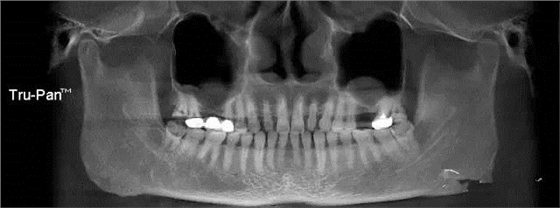

第八圖:有間隔的上頜竇。上頜竇底中間有骨間隔,通常增大了上頜竇外提升開窗的困難。 北一種植老師主張開兩個小窗,有些醫(yī)生也可以開W型窗,來降低難度。